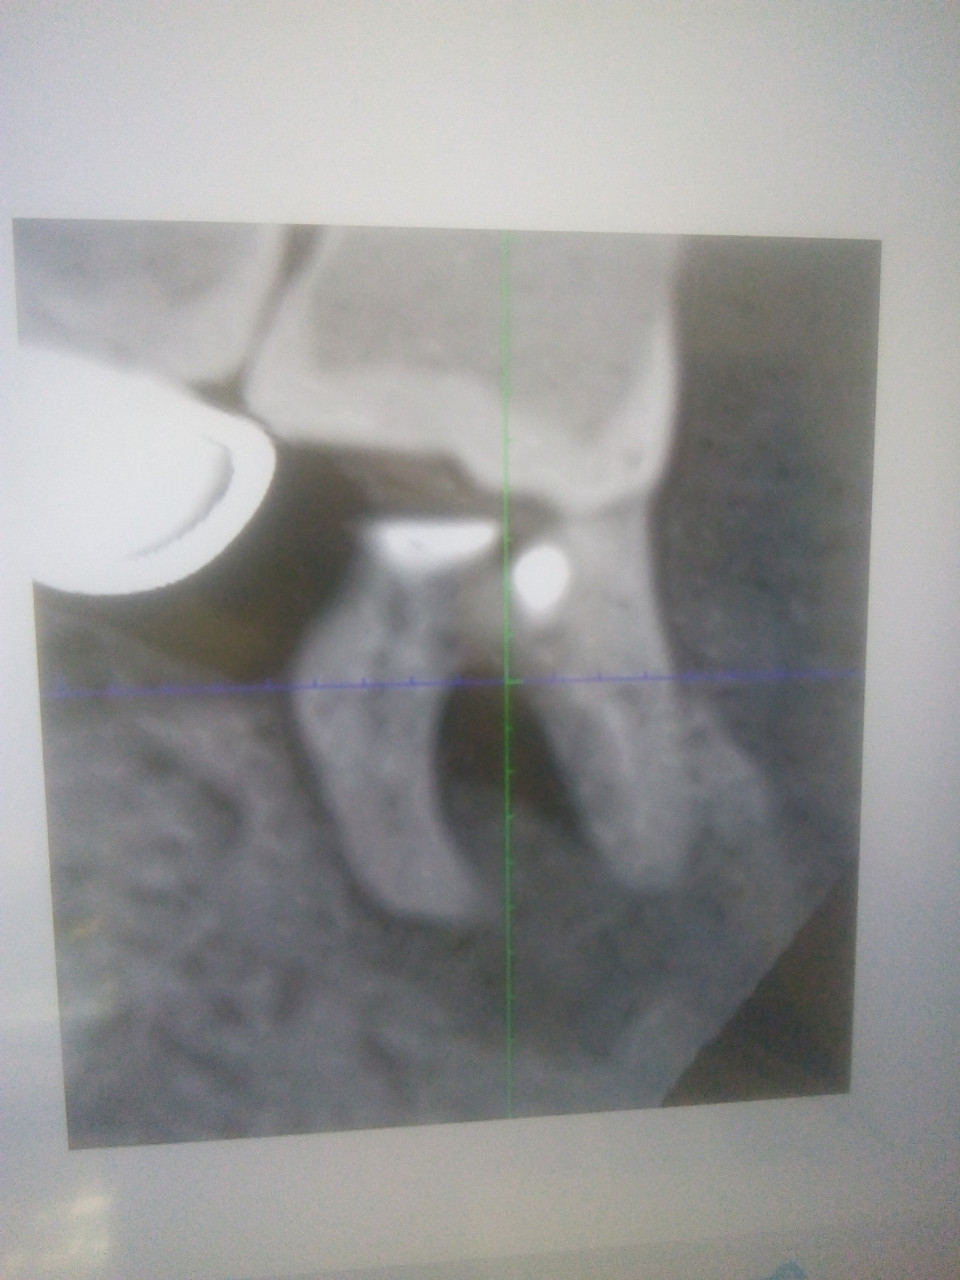

После употребления сухой воблы зуб не сильно болел 3 дня,потом успокоился,но при употреблении жесткой пищи больно.На тепло и холод зуб не реагирует но при нажатии или постукивании ощущается боль.

Здравствуйте. По снимку видно воспаление у корня и возможно проблемы с заполнением канала. Боль при нажатии указывает на периодонтит. Зуб нужно лечить и скорее всего потребуется повторная обработка каналов или удаление. Обратитесь к стоматологу как можно скорее, затягивать не стоит.